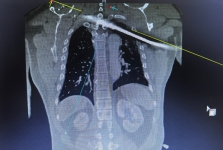

• 四川观察:男子遭钢筋穿胸 省医院多学科联合开展“毫米级”手术

2025-11-25 四川观察:男子遭钢筋穿胸 省医院多学科联合开展“毫米级”手术

• 今日头条:钢筋穿胸命悬一线 四川省人民医院多学科专家协作挽救患者生命

2025-11-25 今日头条:钢筋穿胸命悬一线 四川省人民医院多学科专家协作挽救患者生命